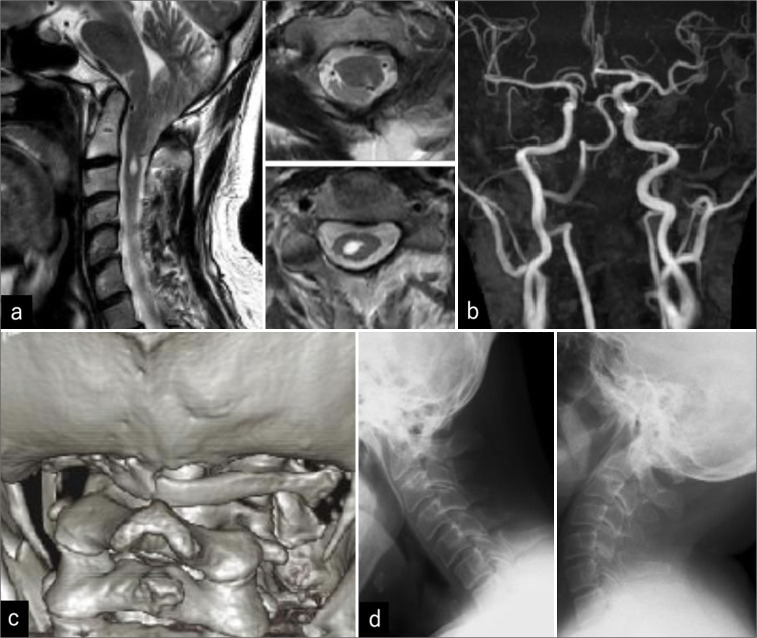

背景:咳嗽性晕厥、中枢性睡眠呼吸暂停(CSA)和伴有寰椎同化的Chiari 1型畸形(CM1)在成人中非常罕见。病例描述:一名48岁男性出租车司机晕倒。他的神经系统是完整的,但经多面体图检测,轻度睡眠呼吸暂停呈阳性。磁共振成像诊断为CM1伴脊髓空洞和寰枕。患者在7年后接受了大枕骨孔减压/C1椎板切除术,并保持完整。结论:1例48岁男性晕厥后出现咳嗽性晕厥、CSA和CM1;在枕骨大孔减压/C1椎板切除术后,患者在接下来的7年中保持神经系统稳定。

Case description: A 48-year-old male taxi driver fainted. He was neurologically intact, but tested positive for mild sleep apnea confirmed by a polysonogram. The magnetic resonance imaging diagnosed a CM1 with syringomyelia and atlas occipitalization. The patient underwent an uneventful foramen magnum decompression/C1 laminectomy and remained intact 7 years later.